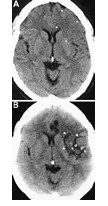

图1 卒中溶栓后出血

卒中发生后3小时内,可见左额叶处灰阶差消失的低衰减区域(图A箭头处)。rt-PA溶栓治疗21小时后,可见左额叶、左基底节处及岛叶皮质处左大脑前动脉和左大脑中动脉供应区缺血性梗死灶(图B大箭头处),此外,还可见小面积出血(图B小箭头处)。